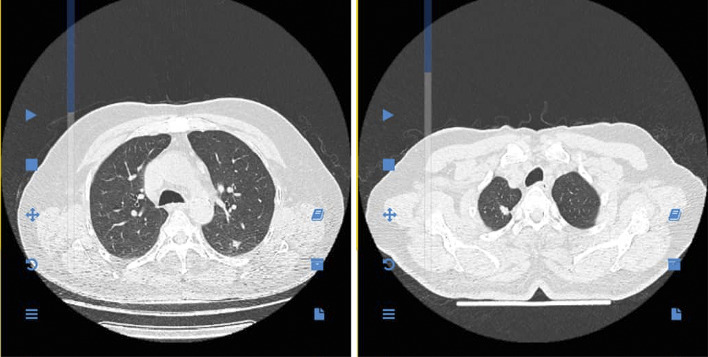

背景:基底细胞癌(BCC)是最常见的皮肤恶性肿瘤,其特点是进展缓慢,转移倾向低。转移性基底细胞癌(mBCC)的发生率不到0.1%,最常累及肺、淋巴结或骨骼。虽然罕见,但mBCC与预后不良有关,并提出了独特的诊断和治疗挑战。病例介绍:我们报告一名77岁男性,患有多发性头颈部基底细胞癌,包括侵袭性组织学亚型(基底鳞状和微结节状),主要采用Mohs手术治疗;切缘状态因手术而异(有的无肿瘤,有的呈阳性)。最初病变十年后,患者出现进行性呼吸困难,胸部CT发现双侧肺结节。PET/CT显示FDG摄取增加,CT引导下右肺结节活检证实mBCC。在原来的切除部位没有局部复发的证据。p16/HPV研究未在先前的皮肤原发灶上进行。结论:本病例强调了BCC迟发性肺转移的可能性,甚至在明显治愈治疗后数年。没有局部复发和双侧肺受累提示血行性扩散。临床医生应该对有高危基底细胞癌病史的患者的转移性疾病保持警惕,特别是当出现新的肺部症状时。成像和免疫组织化学对诊断至关重要,早期发现可以改善这种罕见的侵袭性表现的治疗效果。在该患者中,侵袭性组织学亚型和既往阳性切缘的存在可能增加转移风险。

Background: Basal cell carcinoma (BCC) is the most common cutaneous malignancy, characterized by slow progression and a low propensity for metastasis. Metastatic basal cell carcinoma (mBCC) occurs in fewer than 0.1% of the cases, most frequently involving the lungs, lymph nodes, or bones. Although rare, mBCC is associated with poor prognosis and presents unique diagnostic and therapeutic challenges. Case Presentation: We report a 77-year-old male with a remote history of multiple head-and-neck BCCs, including aggressive histologic subtypes (basosquamous and micronodular), treated predominantly with Mohs surgery; the margin status varied across procedures (some tumor free and some positive). Ten years after the initial lesion, the patient developed progressive dyspnea and was found to have bilateral pulmonary nodules on chest CT. PET/CT demonstrated increased FDG uptake, and a CT-guided biopsy of the right lung nodule confirmed mBCC. There was no evidence of local recurrence at the original excision sites. p16/HPV studies were not performed on the prior cutaneous primaries. Conclusion: This case highlights the potential for delayed pulmonary metastasis in BCC, even years after apparently curative treatment. The absence of local recurrence and the bilateral lung involvement suggest hematogenous spread. Clinicians should remain vigilant for metastatic disease in patients with a history of high-risk BCC, particularly when new pulmonary symptoms arise. Imaging and immunohistochemistry are critical for diagnosis, and early detection may improve therapeutic outcomes in this rare and aggressive manifestation. In this patient, the presence of aggressive histologic subtypes and prior positive margins likely increased metastatic risk.